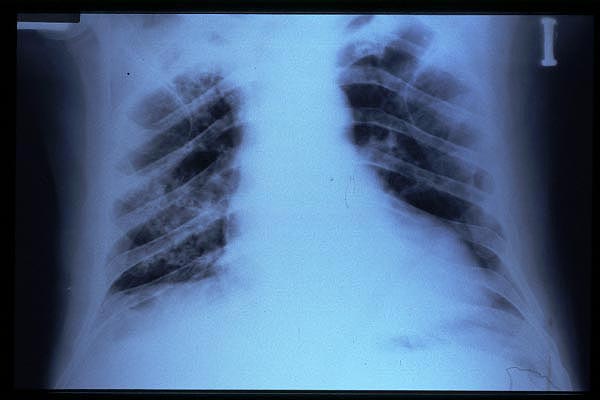

TBC pulmonar antigua